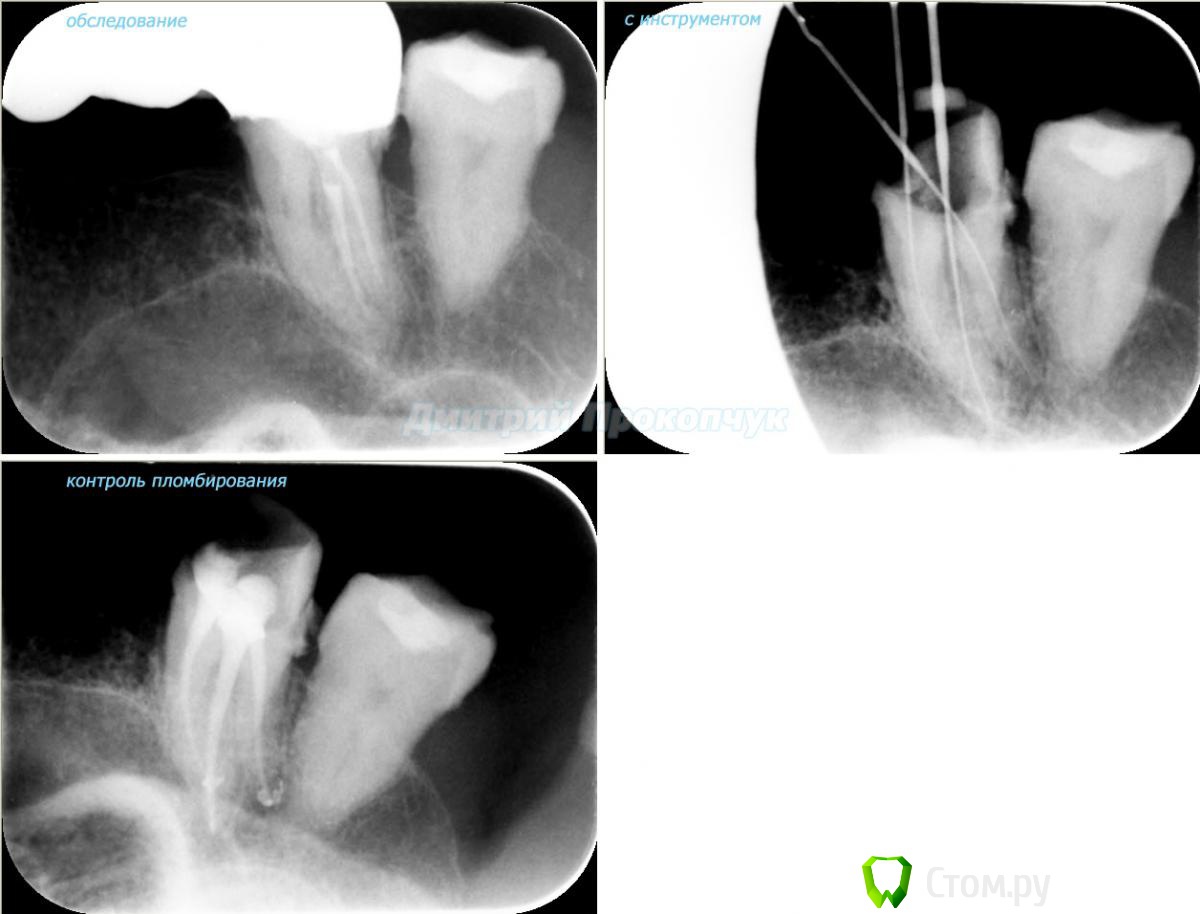

punkrat Опубликовано 16 сентября, 2014 Поделиться Опубликовано 16 сентября, 2014 Коллеги, тема , возможно, не имеет смысла просто приятная мне эндодонтия, сохранил с предыдущего места работы. Да, будь я проклят, я все знаю, НИГДЕ НЕТ КОФЕРА, на новом месте с этим норм. В общем если посчитаете, что я недостоин постить тут свои снимки, то так тому и быть, удалю тему.. 01. плановый ретрит 46ого и результат через 7 месяцев. Осложняющим моментом тут было то, что длина каналов была около 26 мм... 02. первичное эндо 34 (подготовка к ортопедии) + бонус - ретрит 35 03. ретрит 26 (подготовка к ортопедии) 04. ретрит 15, 16 (подготовка к ортопедии). основная сложность была в ретрите 15 - он был запломбирован термафилами, да еще снабжен свш... 05. ретрит 27 (подготовка к ортопедии). Ничего особенного, со временем посмотрим какова будет убыль этого совсем немаленького разрежения 06. ретрит 13. Разумеется пришлось выбивать вкладку, а потом еще попилить 3-4 миллиметра цемента, но, таки попилил куда нужно... 07. ретрит 17 (подготовка к ортопедии). В данном случае я, кажется, потратил больше времени на снятие литого моста, чем на лечение 17)) 08. ретрит 16 (подготовка к ортопедии). Снимка с инструментом нету, поскольку, визиограф сломался и его делал на пленку. 15 разумеется тоже перелечен... 09. плановый ретрит 16 10. первичное эндо 36, рядовой случай что дистальный щечный удалось найти не сразу, он был спрятан под нависающим дентиклем 11. ретрит 12, 11 (подготовка к ортопедии). Казалось бы, рядовой случай, если бы корневые каналы обоих зубов не были бы налухо забиты резорцин-формалиновой смесью... 12. ребенок 9ти лет, острый пульпит 46, попробовал оставить витальным. Пока полет нормальный, но даже если придется делать эндо в последствии, лучше когда оно будет сделано в более старшем возрасте... 13 Ссылка на комментарий